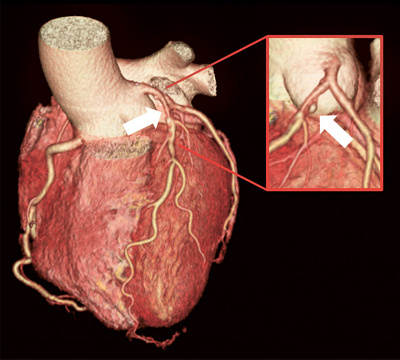

Abb. 2

Herz-MRT: Nachweis einer Minderdurchblutung des Herzmuskels unter Belastung im Vergleich zur Ruhe­aufnahme (weisser Pfeil/schwarze Fläche).